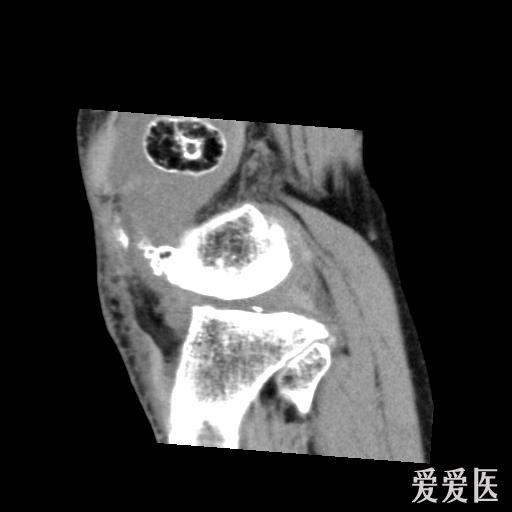

股骨远端骨肿瘤

图片尺寸2048x1536